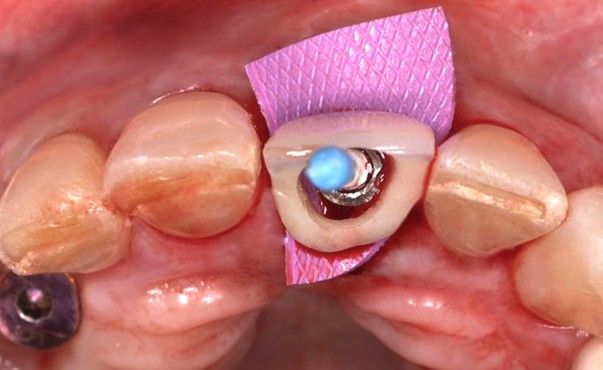

Tras la colocación del implante, se instaló un pilar transepitelial Klockner® tipo Permanent, recto unitario NV de 2 mm de altura, atornillado con un torque de 30 N/cm. Posteriormente, mediante un casquillo provisional de titanio atornillado, se llevó a cabo la recaptura de la corona provisional tipo “cáscara de huevo” previamente confeccionada por el laboratorio (Figura 7). Para ello, se empleó acrílico autopolimerizable (TAB 2000, Kerr®), seguido de la aplicación de composite fluido (Tetric EvoFlow® A2, Ivoclar Vivadent®) para la conformación progresiva del perfil de emergencia, garantizando un adecuado ajuste, acabado y pulido de la restauración provisional (Figura 8 y 9). Dado que las cargas oclusales resultan desfavorables en este tipo de casos, se redujeron los contactos en máxima intercuspidación y durante los movimientos excursivos en el provisional de carga inmediata, con el objetivo de minimizar los micromovimientos y preservar el éxito del tratamiento. La paciente acudió a revisión a los 15 días para retirada de sutura, sin registrar complicaciones en este periodo de tiempo (Figura 10).

El implante se mantuvo en fase provisional durante un periodo aproximado de cuatro meses desde su colocación. Tras esta fase de provisionalización, se realizó la toma de impresión analógica mediante un coping de impresión personalizado, diseñado para reproducir de forma precisa el perfil de emergencia previamente modelado con la restauración provisional (Figuras 11 y 12). A partir de estos registros, se confeccionó e instaló la corona definitiva atornillada, con una oclusión suavizada para evitar sobrecargas del implante (2.1i). La imagen clínica (Figuras 13 y 14) y el CBCT postoperatorio (Figura 15) evidencian una situación clínica y radiológica favorable, con estabilidad de los tejidos periimplantarios a los cuatro años de seguimiento.